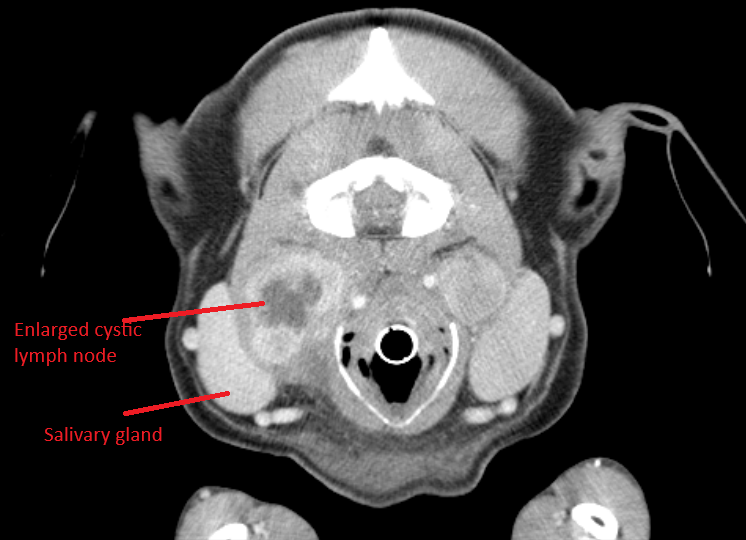

5 wks ago my boy Olaf received a shock cancer diagnosis – stage III/IV tonsillar squamous cell carcinoma, which comes with poor prognosis and a median survival time of ~100 days

3 wks ago an incredible surgical team removed his left tonsil, its 2 cm tumour, and 4 malignant lymph nodes the size of kiwi fruit

2 days ago we had our first consult with oncology, and based on the margins + histopathology there’s a small but real chance at definitive treatment. so we’re going to fight